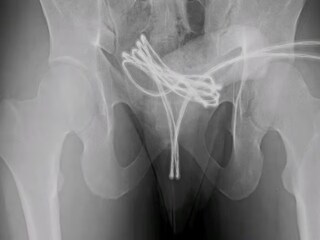

जेव्हा डॉक्टरांनी तपासणी केली, तेव्हा आढळले की केबल मूत्राशयात पोहोचली होती आणि तिथेच अडकली होती. 'क्युरियस' जर्नलमध्ये प्रकाशित झालेल्या अहवालानुसार, डॉक्टरांनी आधी हाताने केबल काढण्याचा प्रयत्न केला, पण ते यशस्वी झाले नाहीत. शेवटी, मुलाला बेशुद्ध करून विशेष उपकरणांच्या मदतीने केबल काढण्यात आली. डॉक्टरांनी हळू हळू केबल बाहेर ओढली, नंतर ती कात्रीने कापली आणि दोन्ही भाग सहज बाहेर काढले.